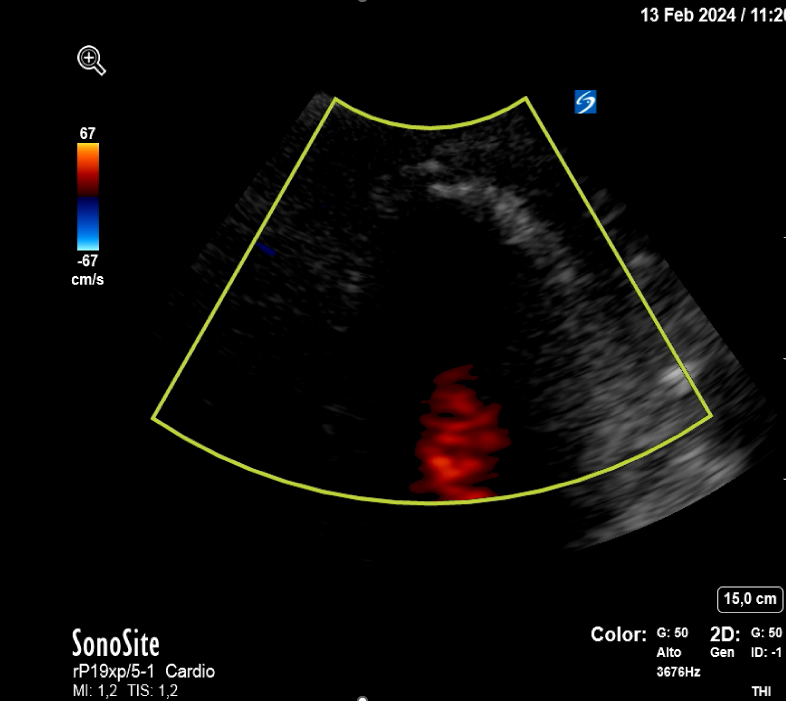

Se realiza interconsulta a Cardiología quien realiza una ecografía clínica cardíaca a pie de cama objetivando acinesia en ápex del ventrículo izquierdo con falta de continuidad a nivel septo-apical con flujo doppler compatible con rotura cardíaca a nivel de ápex que origina un derrame pericárdico moderado-severo, con colapso de ventrículo derecho.

La estabilización hemodinámica junto a los parámetros clínico-ecográficos indican un taponamiento fibrinoso de la rotura cardíaca. Se decide ingreso en planta de medicina interna tras pico de troponina de 7000 pg/mL con el diagnóstico rotura cardíaca contenida. A las 10 horas de la 2ª ecografía clínica y antes de su traslado a una planta médica, se realiza una tercera ecografía clínica dirigida estando el paciente consciente, estable sin dolor. En el mismo se aprecia el mismo derrame pericárdico moderado idéntico al objetivado previamente, pero hay un nuevo hallazgo en el ápex del VI: un trombo intracavitario adherido (imagen 2).